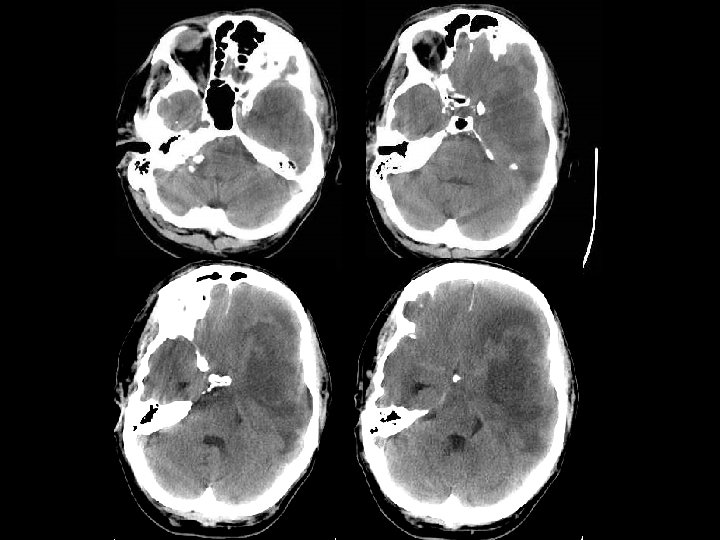

CONTUSION/LACERATIONS n Sumber tersering SAH traumatik n Contusion : harus melibatkan superficial gray n n matter Laceration: contusion + robekan piaarachnoid Mempengaruhi the crests of gyri Perdarahan dijumpai pada 50% kasus dan timbul pada sudut yang tepat terhadap permukaan kortikal Terletak dekat kontur tulang yang ireguler : poles of frontal lobes, temporal lobes, inferior cerebellar hemispheres

Intraparenchymal hematoma n Kumpulan darah fokal yang tersering timbul dari shear-strain injury pada pembuluh darah intraparenkim n Umumnya berlokasi pd frontotemporal white matter atau basal ganglia n Hematoma di dalam parenkim otak yang normal n DDx: DAI, hemorrhagic contusion